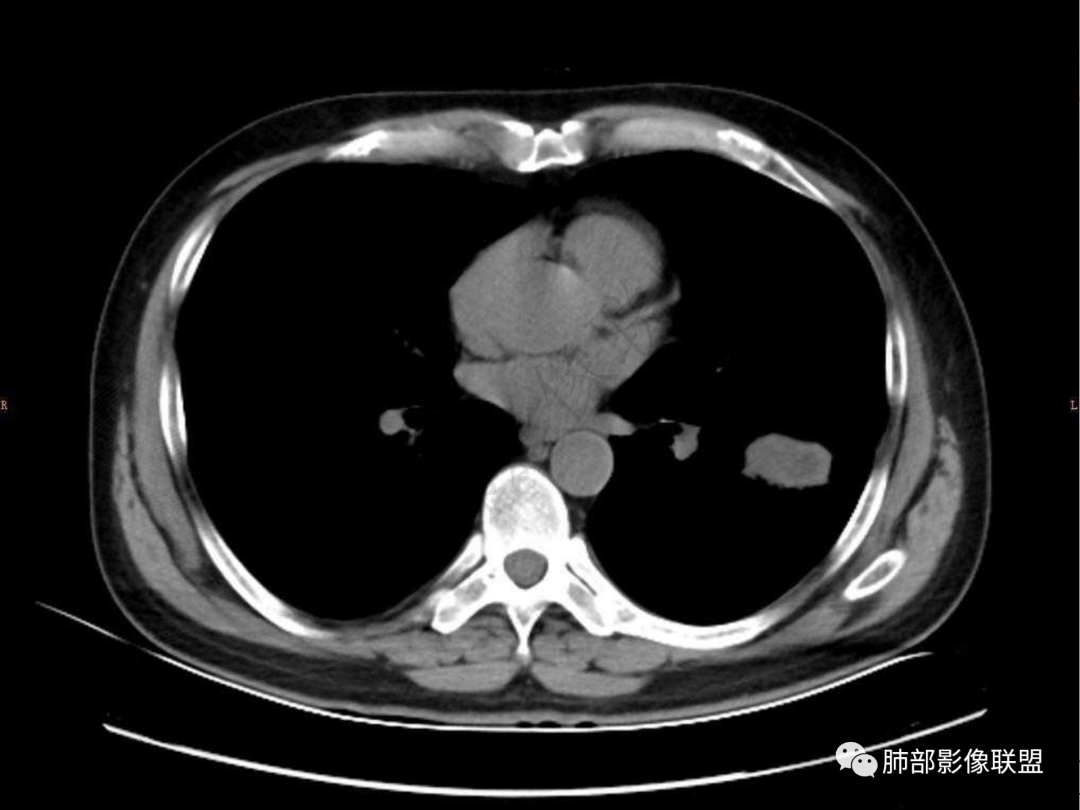

1.中年男性,咳嗽咳痰20余天,间断咯血2周

2.左肺下叶团片影,跨背段及内前基底段,实性部分类椭圆形,密度不甚均匀,可见毛刺及棘状突起,未见典型分叶及胸膜凹陷。病灶上下缘可见相应肺段支气管旁进侧出,管壁轻度增厚,未见狭窄阻塞。

3.周边较大范围磨玻璃影,边界相当模糊,小叶增厚明显。注意叶裂另一侧、左肺舌段亦可见磨玻璃影及增厚的小叶间隔。未见明确卫星病灶。

4.实性部分不均匀环形强化并显示一小范围低密度坏死区或空洞。较之肺窗,整体纵隔窗范围较小,提示病灶并不十分密实。抑或为不同时段图像。

5.双肺门及纵隔未见增大淋巴结。未见胸腔积液。